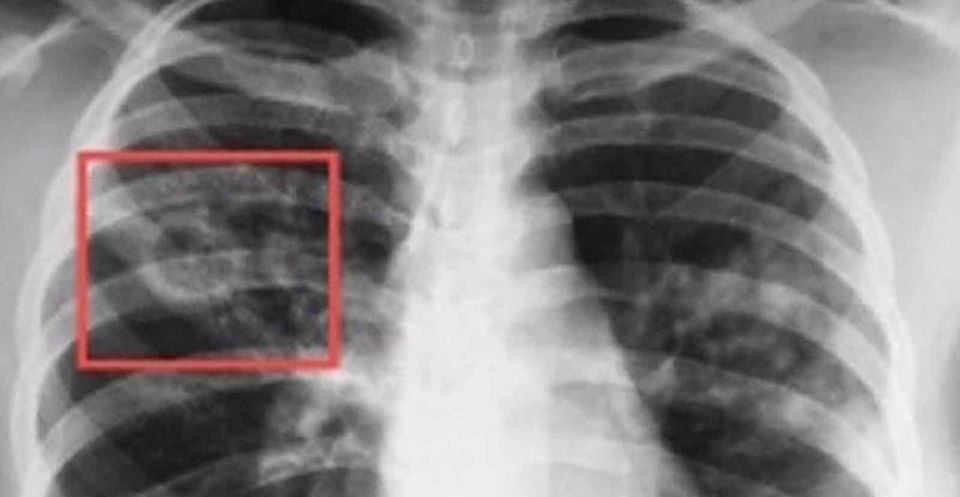

В Новосибирске открыли первое в Сибири паллиативное отделение для больных туберкулезом: 4 палаты с холодильниками и небольшими телевизорами, на окнах – цветные шторы. Часть из 15 коек пока пустуют. Это ненадолго, говорит главный врач областной туберкулезной больницы Анна Пятибратова. В Новосибирской области ежегодно только от туберкулеза погибают 300 человек, еще 200 – от туберкулеза на фоне сопутствующих болезней, чаще всего это ВИЧ.

«Почему-то считается, что туберкулез – достаточно редкое заболевание. У нас к нему как-то спокойно относится население, – рассказывает Анна Пятибратова. – Но, как бы то ни было, это одна из 10 основных причин смерти. В Новосибирской области ежегодно от него умирает до 500 человек. Повышение качества медицинских услуг туберкулезным больным, в том числе оказание паллиативной помощи является одной из основных задач регионального здравоохранения. Наши пациенты представляют эпидемиологическую опасность для других больных и для населения в целом. Поэтому они не могут находиться в обычном паллиативном отделении, они должны находиться в противотуберкулезных учреждениях. Данное отделение первое в Сибирском федеральном округе, будем нарабатывать опыт, возможно, придется увеличивать количество коек. Следующий этап – развитее амбулаторной, патронажной паллиативной помощи».

«Решение о переводе пациента в паллиативное отделение принимается Центральной врачебной комиссией действующей на базе областного противотуберкулезного диспансера, говорит заведующий филиалом ГБУЗ НСО ГОНКТБ «Туберкулезная больница №1 Дмитрий Степанов. - Паллиативный режим предусматривает лечение противотуберкулезными и иными препаратами, позволяющий обеспечить комфортную жизнь больным, которым по медицинским показаниям невозможно найти методы лечения, которые приведут к полному выздоровлению. Наше отделение улучшит качество жизни пациентов и членов их семей, столкнувшимися с проблемами тяжелого, неизлечимого заболевания. Дело в том, что больные туберкулезом в терминальной стадии не только испытывают страдания сами, они еще представляют опасность для окружающих, в активной форме заболевания происходит выделение микобактерий туберкулеза в окружающую среду. Им требуется интенсивное лечение, многие их них не могут обходиться без кислородной поддержки. Многим нашим пациентам требуется не только врачебная, но и особая сестринская помощь. В больнице приобретено все необходимое оборудование для врачебного контроля, ухода за больными и проведения гигиенических процедур.»